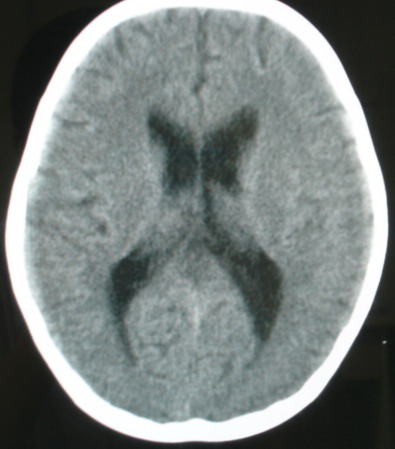

m/8y/,右侧眼睑下垂数日,发育良好,无外伤史,无头痛、恶心、呕吐,学习成绩良好。

ct意见:1、颅内血管畸形。2、右侧海绵窦血管瘤(颈内动脉海绵窦段动脉瘤)。3、脑萎缩。4、建议mr或dsa.

增强片